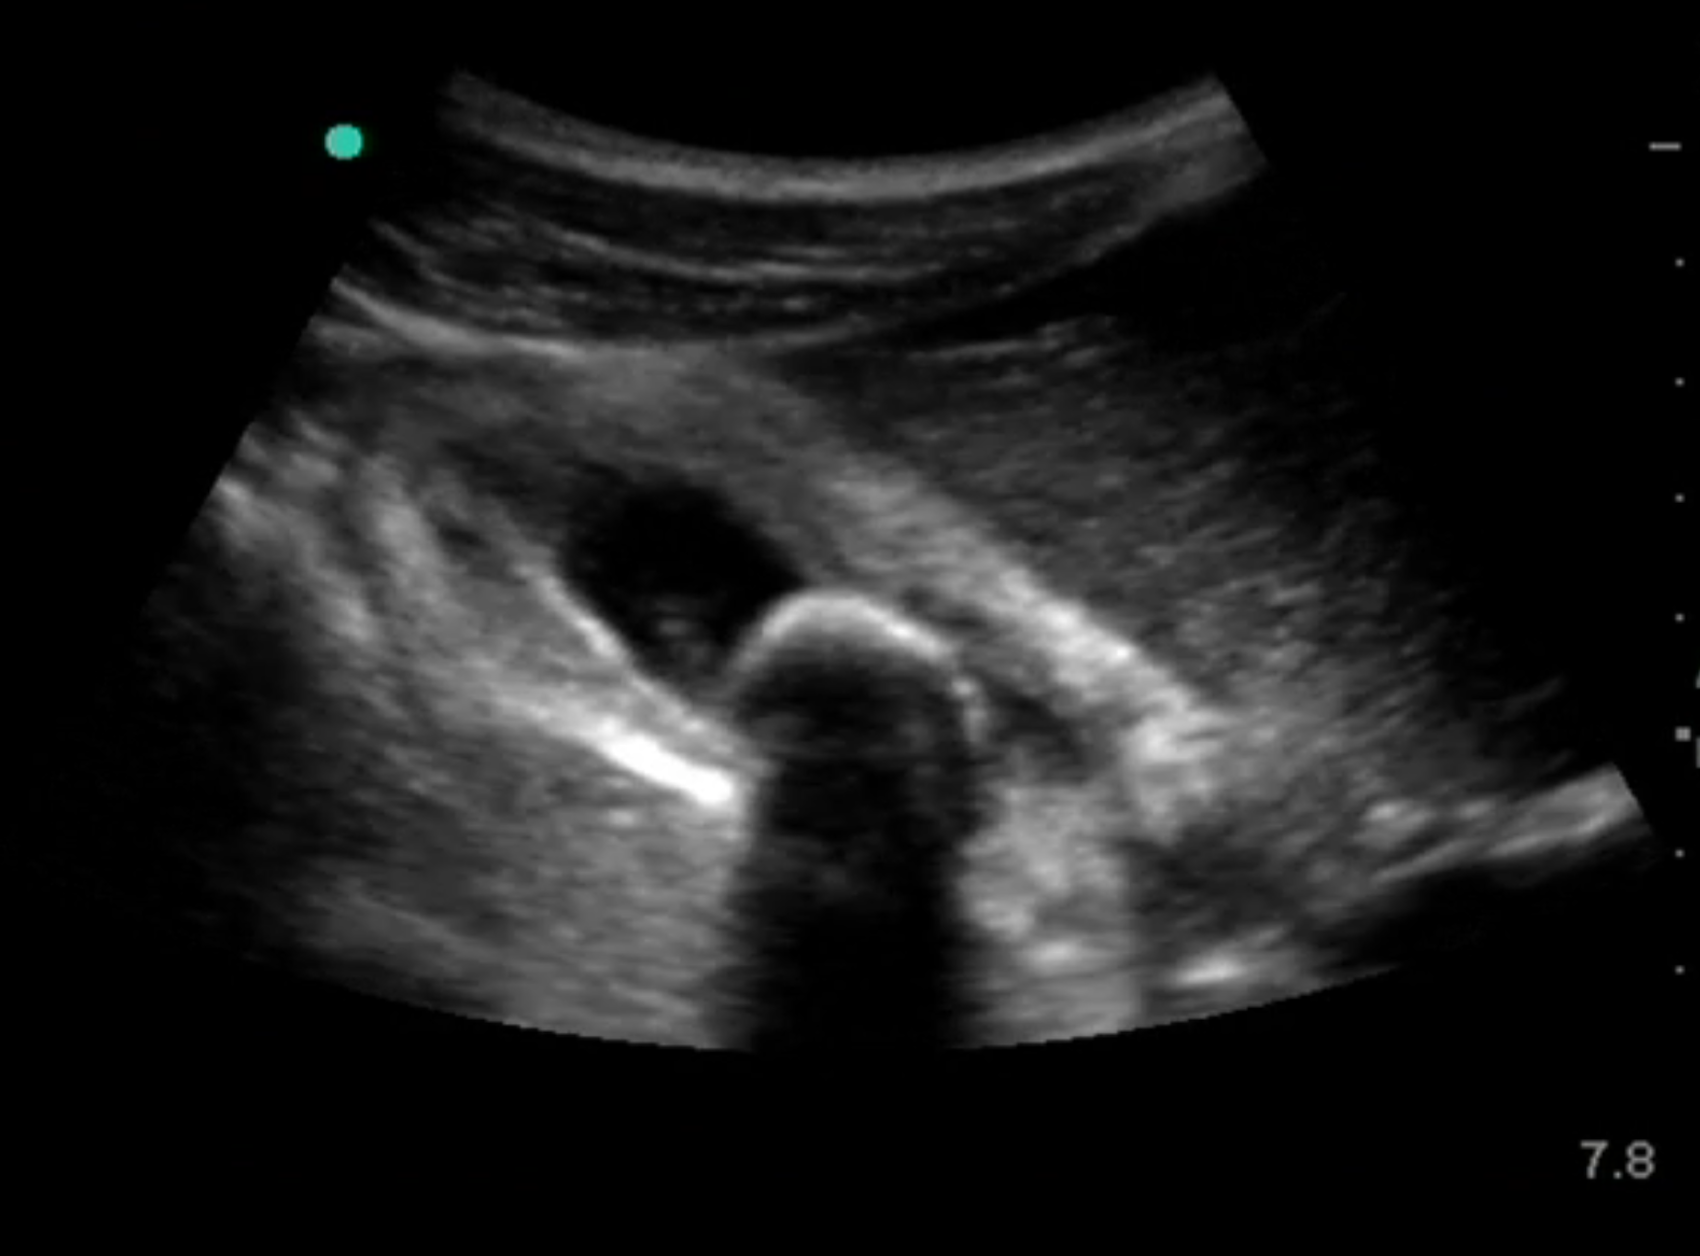

Bild: Gallenblase, akute Cholezystitis mit Gallenstein